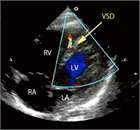

1. 心室中隔欠損は、欠損孔の部位により、膜性周囲部(perimembranous)、筋性部(muscular)、漏斗部または肺動脈弁下部(subarterial)に分類され、自然歴、手術適応が各々異なるため、部位診断は重要である。

1. 心室中隔欠損は自然閉鎖する場合もあるが、心不全症状を有する、あるいは肺高血圧を合併する場合、漏斗部欠損で大動脈弁の逆流を呈する場合は、外科手術の適応となる(推奨度1)。Eisenmenger症候群を呈すると手術適応がなくなるので、その前に適切な治療時期を逃さないことが大切である。